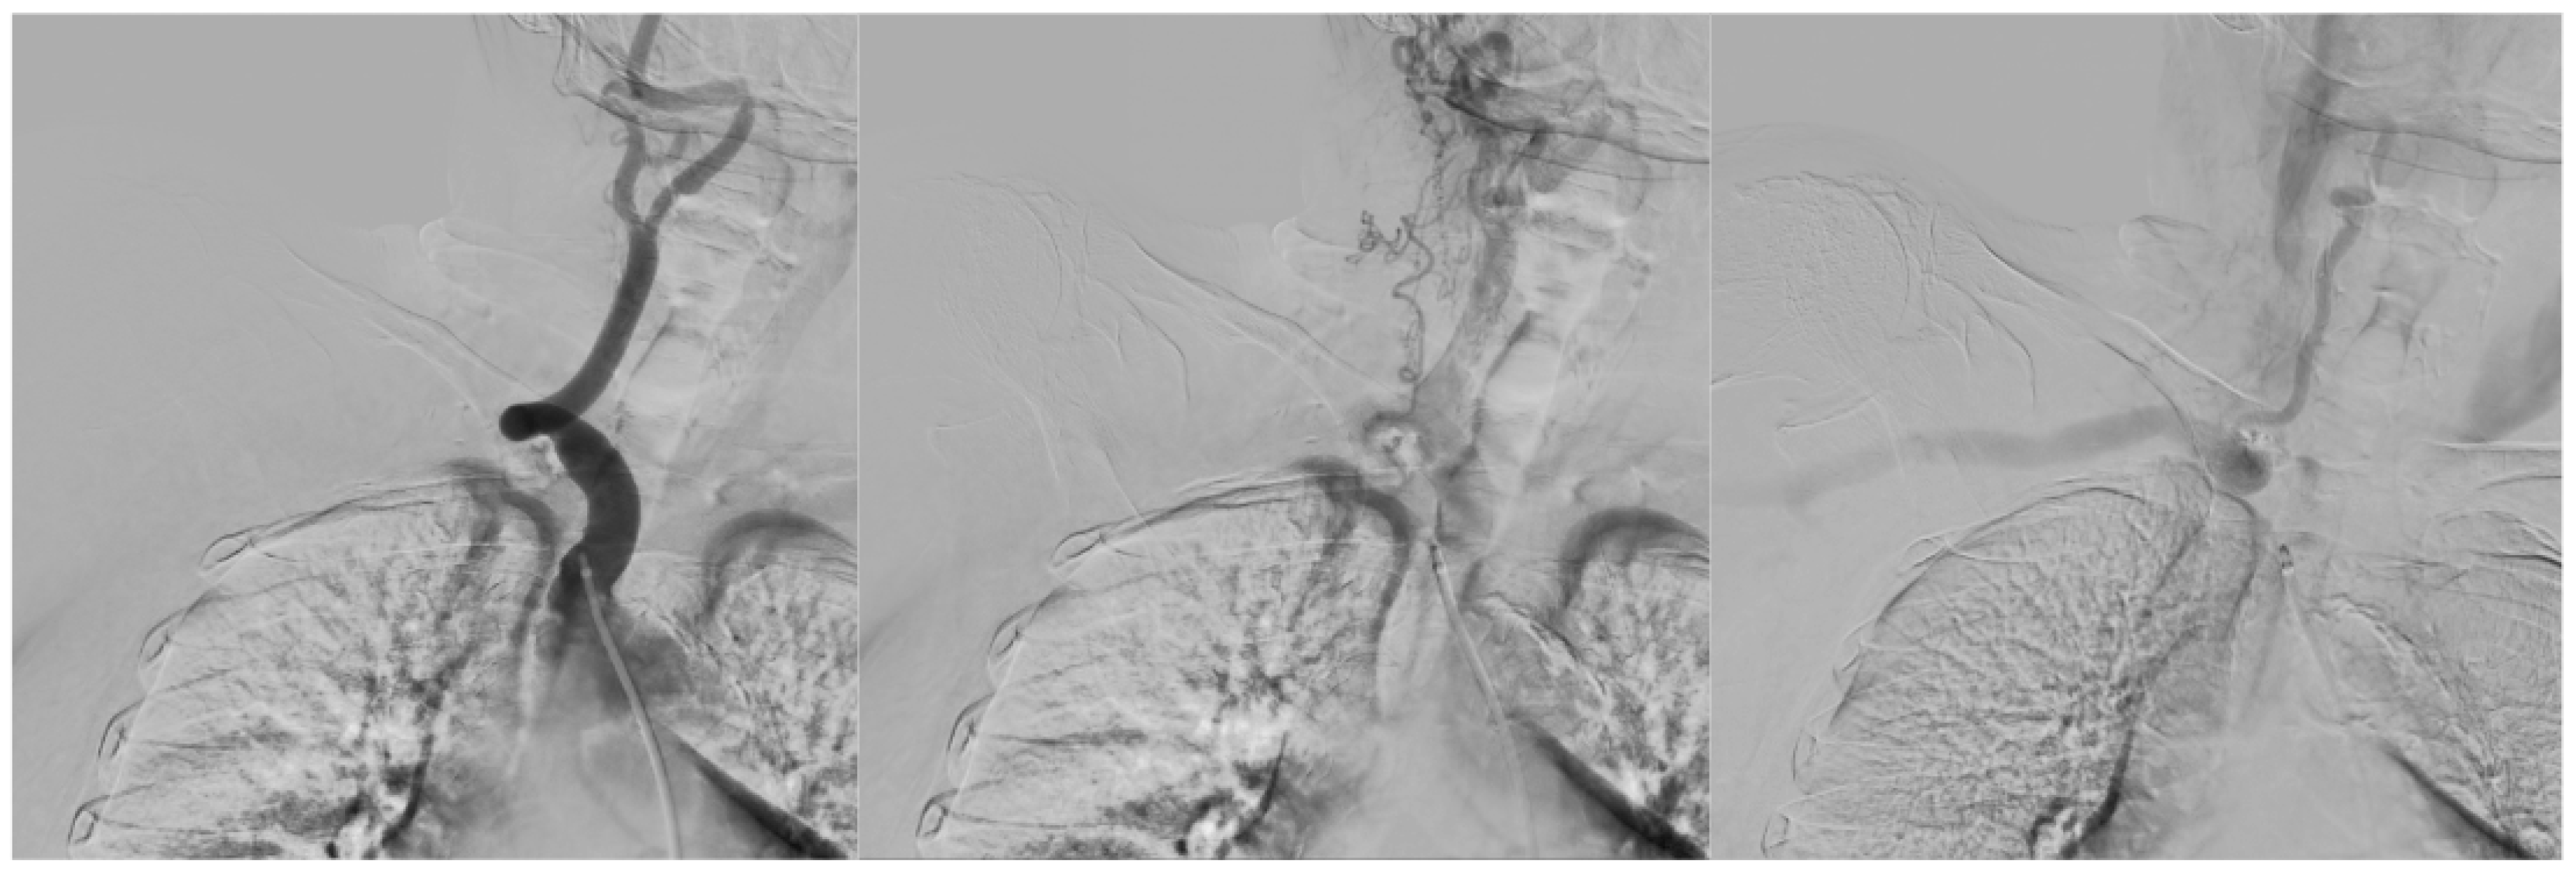

- Interventional Radiology – an attempt at recanalization of the right subclavian artery